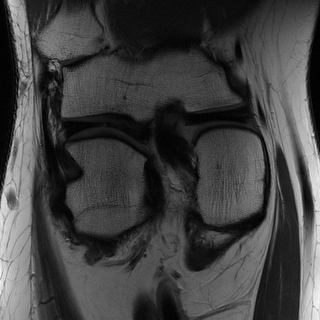

Edge preserving has always been a crucial concern in the design of reconstruction models. To improve the quality of reconstructed images and preserve image edges, some works suggested introducing edge priors in the original restoration problem to preserve image edges [4, 34]. However, they will suffer from complicated algorithm design and time-consuming training processes. Recently, some more efficient methods have been proposed to use edge maps as external guidance for image restoration. For example, Yang et al. [48] used off-the-shelf edge detectors to extract image edges from the degraded images. Fang et al. [12] predicted image edges by constructing an edge reconstruction network. Huang et al. [18] designed a novel dual discriminator GAN framework for solving fast multi-channel MRI, in which one GAN network is built for edge information enhancement. Inspired by these methods, we also consider introducing image edge prior as external guidance to MRI reconstruction since 1) image edges are prominent and distinguishable features in MRI (see Fig. 1), which can serve as a good guide to the model to recover high-frequency details; 2) the ground truth edges can be easily fetched via ordinary edge extraction operators, like Canny, Sobel, and Prewitt, which means that the edge maps can be learned in a data-driven manner. However, how to effectively utilize image edge priors to guide image reconstruction still remains a challenge. In some methods, edge information was simply concatenated with the input image and passed to the next stages. Though this is a simple way to utilize the edge priors, it may not give full play to the guiding role of the edge priors. Therefore, in this work, we want to explore a more efficient and effective mechanism to fully take advantage of image edge priors.

(a)

(b)

(c)

fastMRI is a large-scale MR dataset jointly established by Facebook AI Research and NYU Langone Health. It provides both knee and brain datasets for evaluation. In our work, we use the multi-coil knee dataset, which was acquired on three clinical 3T systems or one clinical 1.5T system using a 15-channel knee coil array. The dataset includes data from two pulse sequences, yielding coronal proton-density weighting with (PDFS) and without (PD) fat suppression. As is shown in Fig. 1, PD images usually contain more structural and prominent edge features than PDFS images, which suggests that it is more challenging to use edge guidance on PDFS datasets. Therefore, we explore the effectiveness of EAMRI on these two modalities. Following [13], for both PD and PDFS knee datasets, we separately filter out 227 volumes (8332 slices) for training and 24 volumes (1665 slices) for testing. The dataset is centrally cropped to .